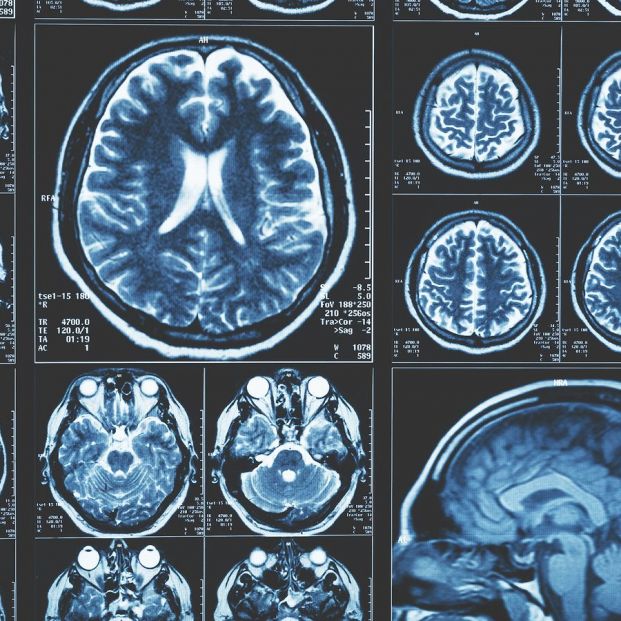

El diseño de este trabajo ha permitido a los investigadores examinar las imágenes cerebrales de tres generaciones de participantes con fechas de nacimiento que abarcan 40 años.

La investigación, publicada en la revista 'JAMA Neurology', cuenta con la primera autoría de Charles DeCarli, profesor de neurología y director del Centro de Investigación de la Enfermedad de Alzheimer de UC Davis . En ella, se compararon las resonancias magnéticas de personas nacidas en la década de 1930 con las de nacidos en la de 1970.

Los investigadores utilizaron imágenes de resonancia magnética (IRM) del cerebro de los participantes en el Framingham Heart Study (FHS).

En las imágenes, se observaron aumentos graduales pero constantes en varias estructuras cerebrales. Por ejemplo, una medida que analizaba el volumen cerebral (volumen intracraneal) mostraba aumentos constantes década tras década.